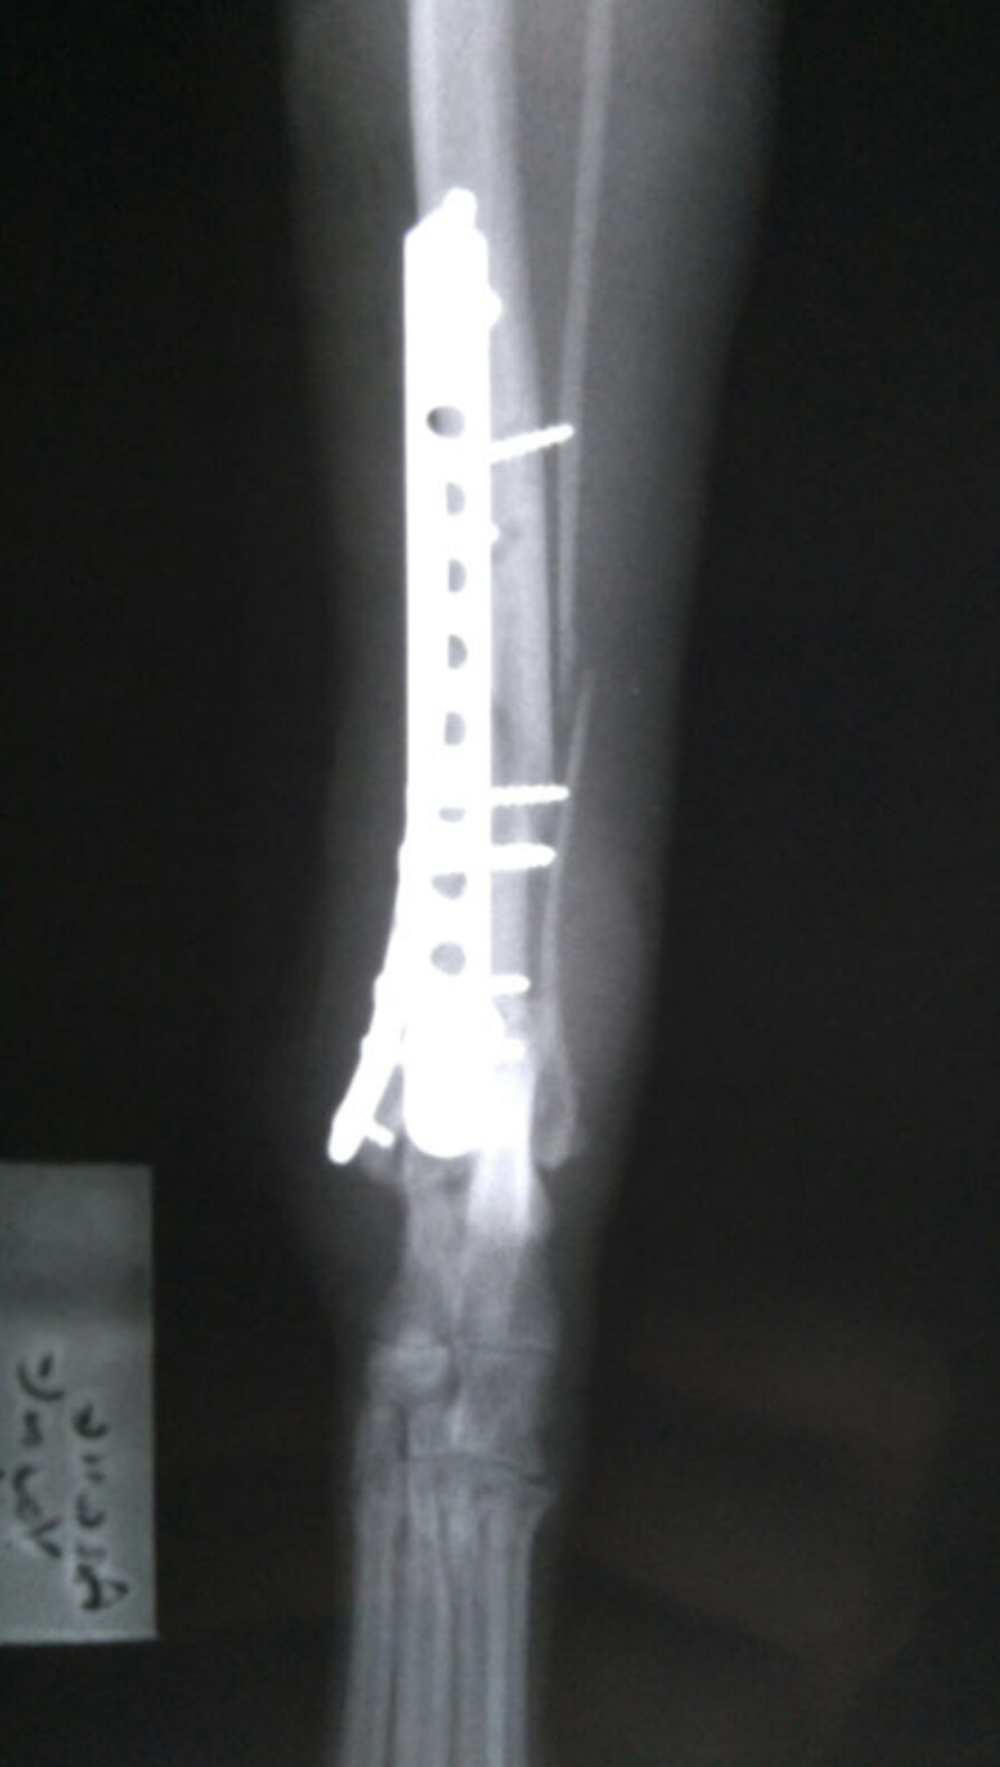

Radius and Ulna Fracture Repair

Example of Minimally Invasive Radius and Ulna Fracture Repair.